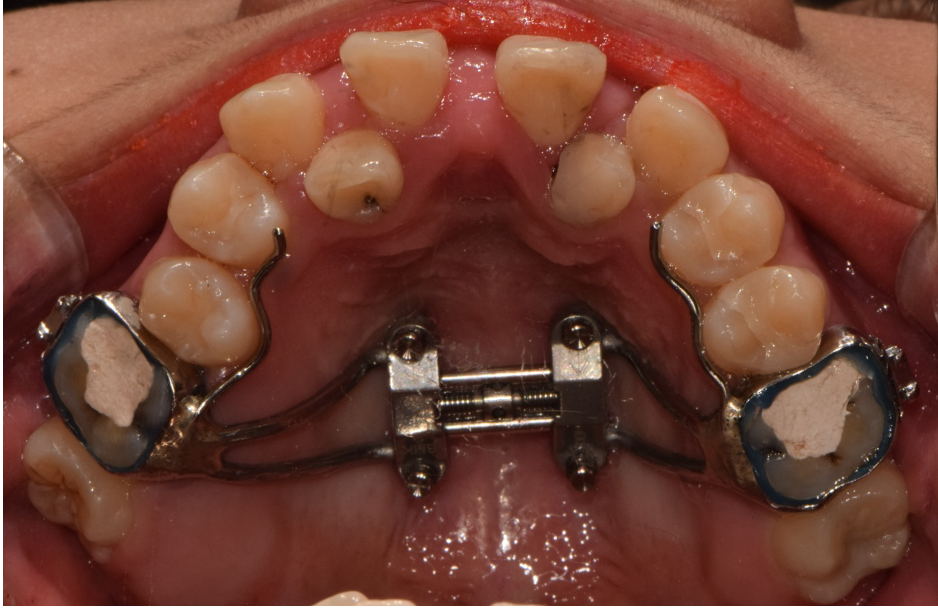

상악 악궁이 좁을 경우에는 하악을 편안하고, 안정적으로 수용하지 못하기 때문에 치아의 배열이 고르지 못하고, 이로 인해 돌출입, 주걱턱과 같은 문제가 생기게 됩니다. 이러한 경우 악궁확장을 통해 미리 증상을 예방하거나 이미 문제가 발생한 경우 시행하여 안정적이고, 바른 치아배열을 만들 수 있습니다. 아래사진은 주걱턱 개선을 위해 양악 수술을 할 줄 알고 큰 근심을 가진 환자를 상악궁 확장을 통한 비수술-비발치 교정으로 치료한 증례입니다.

좁은 악궁을 가진 케이스

환자의 상태(구개골의 두께, 지대치의 상태 등)를 고려하여 적절한 악궁확장 장치를 사용합니다.